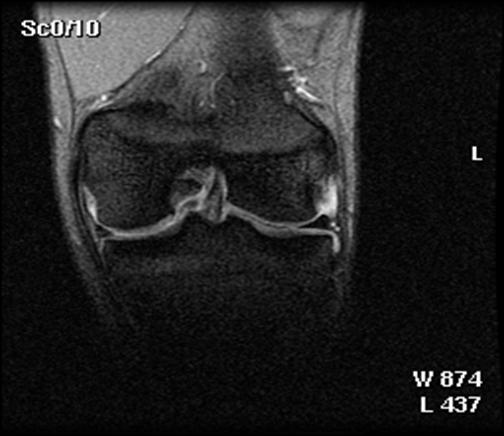

1. Imaginile RMN

Din 48 de pacienti tratati cu tehnica de microfracturare in studiul nostru, 24 (50%) au acceptat sa fie evaluati prin imagini ale rezonantei magnetice. RMN a fost facut doar pentru studiu si nu datorita vreunui simptom clinic si s-a efectuat in medie la 12 2 luni (de la 3 la 36 de luni) dupa operatie. Imaginile au fost executate la mai putin de 6 luni pentru 3 pacienti (13%), de la 6 la 12 luni pentru 15 pacienti (61%) si mai mult de 12 luni dupa microfracturi pentru 6 pacienti (26%). Sase pacienti au o serie de imagini RMN cu media 1,3 0,1 (de la 1 la 3 scanari) pe pacient. La acesti 6 pacienti, descoperirile la cea mai recenta evaluare imagistica au fost folosite pentru analiza rezultatelor functionale. Nu s-au gasit diferente semnificative intre pacientii cu sau fara evaluare imagistica RMN cu privire la datele demografice (p>0,650); caracteristicile leziunilor (p>0,450); durata preoperatorie a simptomelor (p= 0,793); indexul masei corporale (p= 0,217); durata urmarii postoperatorii (p= 0,902); si scorul preoperator si postoperator pentru activitatile zilnice (p=0,250); SF-36componenta fizica (p= 0,250), IKDC (p= 0,820) si rata subiectiva (p = 0,867).

Fig.32. Imagine RMN pacient T.C. 19 ani

Fig.33. Imagine RMN T.C. 19 ani

Fig.34. A-scanare inaintea microfracturarii, B-scanare la patru luni dupaa microfracturare.

Evaluarea imaginilor RMN a fost realizata de catre radiologist cu experienta, care cunostea situatia pacientilor si operatia efectuata. Imaginile au fost astfel analizate incat sa se observe zonele cu cartilaj de reparare comparativ cu cel nativ. Repararea morfologica a fost descrisa ca depresiva, neteda, sau mareata comparativ cu cartilajul nativ inconjurator. Volumul de umplere al defectului cu cartilaj reparator a fost masurat folosind imagini sagitale si coronale si a fost gradat ca bun (intre 67% si 100%), moderat (34% la 66%), sau slab (0% la 33%) pe baza procentajului defectului umplut. Interfata cu suprafata cartilajului nativ adiacent a fost evaluata si gradata ca fiind mica ( gaura ≤ 2mm) sau mare (gaura ˃ 2mm). Edemul maduvei osului subcondral a fost gradat ca fiind usor (˂ 1 cm²), moderat (intre 1 si 3 cm²) sau sever (˃ 3 cm²), iar prezenta sau absenta cresterii osoase a fost atent inregistrata.